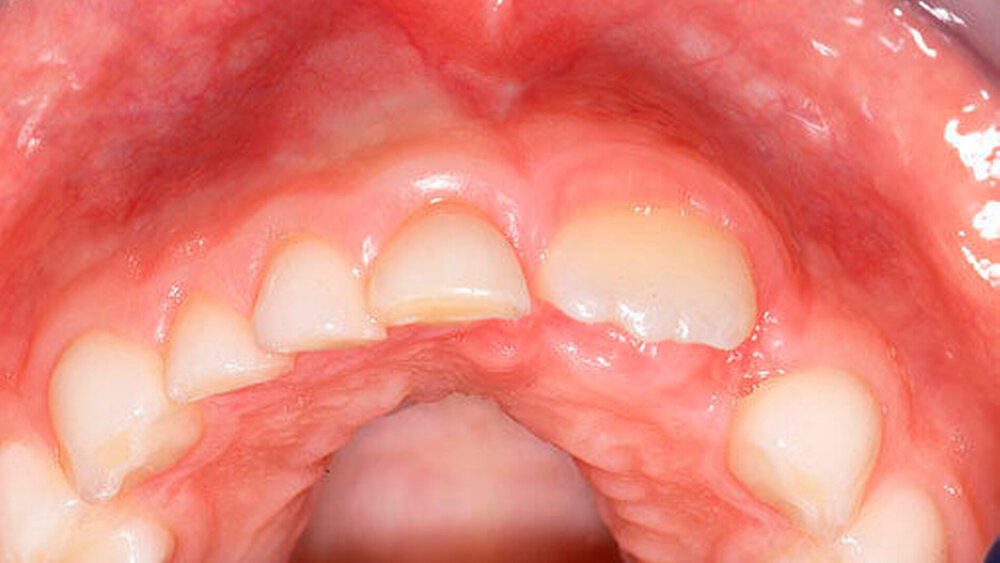

Die Prävalenz überzähliger Zähne wird im Bereich von 0,07 Prozent bis 0,6 Prozent für das Milchgebiss [Luten, 1967; Ravn, 1971; Järvinen Lehtinen, 1981; Magnússon 1984; Skrinjari Barac-Furtinovi, 1991; Yonezu et al., 1997; Chen et al., 2010] und von 0,3 Prozent bis 3,2 Prozent für die bleibenden Zähne [Luten, 1967; Bäckman Wahlin, 2001; Salcido-García et al., 2004; Leco Berrocal et al., 2007; Gündüz et al., 2008; Yagüe-García et al., 2009; Schmuckli et al., 2010; Fardi et al., 2011] angegeben. Die Mehrheit der überzähligen Zähne im Milchgebiss sind seitliche Schneidezähne im Oberkiefer, die meist mit einer normalen Morphologie und Lage durchbrechen (Abbildungen 1 bis 3) [Luten, 1967; Humerfeld et al., 1985; Garvey et al., 1999; Ferrés-Padró et al., 2009]. Der oft ungestörte Durchbruch und das Ausbleiben von Symptomen führen dazu, dass überzählige Zähne in der Milchdentition oft gar nicht diagnostiziert werden, und dies wird auch als Erklärung für die unterschiedlichen Prävalenzen überzähliger Zähne im Milch- und bleibendem Gebiss angeführt [Wang Fan, 2011]. Überzählige Zähne sind häufiger bei Männern als bei Frauen, wobei über ein Verhältnis von 1,18:1 bis 4,5:1 berichtet wird [Rajab Hamdan, 2002; Fernández Montenegro et al., 2006; Gündüz et al., 2008; Wang Fan, 2011]. In der Schweiz publizierten von Arx (1990) und Schmuckli und Mitarbeiter (2010) Geschlechterverhältnisse von 2,6:1, beziehungsweise 2,75:1. In einer aktuellen Arbeit von Mossaz und Mitarbeiter (2014) von Patienten aus dem Raum Bern lag dieses Verhältnis etwas ausgeglichener bei 1,61 zu 1.

Die überzähligen Zähne mit identischer Zahnform finden sich normalerweise beim oberen seitlichen Schneidezahn. Zusätzliche Prämolaren und Molaren können aber auch auftreten. Die Mehrheit der überzähligen Zähne im Milchgebiss sind vom identischen Zahnform-Typ und bleiben nur selten impaktiert oder retiniert.